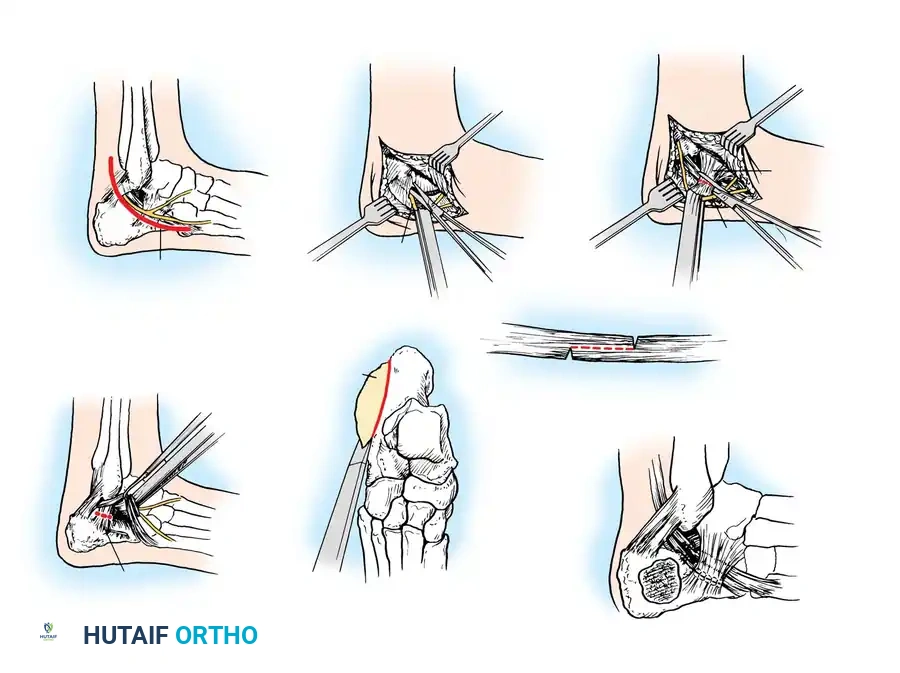

The Extensile Lateral Approach

The workhorse for calcaneal ORIF is the extensile lateral approach.

- Positioning: The patient is placed in the lateral decubitus position. A thigh tourniquet is applied.

- Incision: An L-shaped incision is made. The vertical limb is placed just anterior to the Achilles tendon, and the horizontal limb is placed in line with the base of the fifth metatarsal, transitioning between the glabrous (plantar) and non-glabrous (lateral) skin.

- Flap Creation: A full-thickness subperiosteal flap is elevated. It is imperative to use a "no-touch" technique. Retraction is achieved by placing stout Kirschner wires (K-wires) into the fibula, talar neck, and cuboid, bending them to hold the flap out of the surgical field without using self-retaining retractors that crush the skin edges.

Reduction Sequence

The reduction follows a strict, logical sequence:

- Decompression: The lateral wall blowout is reflected inferiorly to expose the depressed posterior facet and the subtalar joint.

- Tuberosity to Sustentaculum: A Schanz pin is placed into the posteroinferior tuberosity. Using the pin as a joystick, the tuberosity is pulled out of varus, translated medially, and pulled plantarly to restore length, height, and alignment. It is temporarily pinned to the constant sustentacular fragment.

- Posterior Facet Reduction: The depressed articular fragments are elevated to match the intact articular surface of the talus.

- Anterior Process: If the calcaneocuboid joint is involved, it is reduced and pinned.

- Lateral Wall: The lateral wall is reduced to decompress the subfibular space, ensuring the peroneal tendons have adequate excursion.

Internal Fixation

Once anatomical reduction is confirmed via fluoroscopy (including Brodén views), definitive fixation is applied. A low-profile, anatomically contoured calcaneal locking plate is typically utilized.

Screws must be directed from lateral to medial, specifically targeting the dense bone of the sustentaculum tali to anchor the construct.

Percutaneous and Minimally Invasive Techniques

For specific fracture patterns, particularly the Essex-Lopresti Tongue-Type fractures, percutaneous reduction and screw fixation can yield excellent results with minimal soft-tissue risk.

Using the classic Essex-Lopresti maneuver, a heavy Schanz pin or Steinmann pin is introduced percutaneously into the posterior aspect of the tongue fragment. The knee is flexed to relax the Achilles tendon, and the pin is used to lever the fragment plantarly, restoring the posterior facet congruity.

Once reduced, the fragment is secured with percutaneous cannulated screws directed from the posterior tuberosity into the anterior calcaneus.